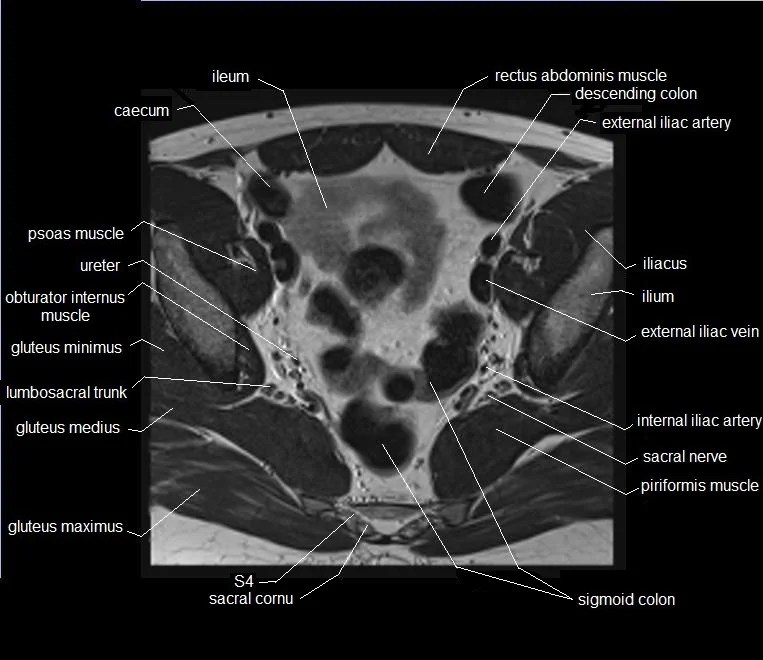

Mri Anatomy Male Pelvis . Anatomy of the male pelvis (prostate, bladder, genital organs, perineum) on mr imaging, male pelvis, mri, urinary system. Mri techniques for imaging the male pelvis; Knowledge of normal pelvic anatomy on mri is critical for proper interpretation, in particular the standard visceral organ appearances, commonly encountered variants, and. The gonadal vessels refer to the testicular artery and testicular vein in males and the ovarian artery and ovarian vein in females. This article reviews normal male pelvic floor anatomy and how it differs from the female pelvis; Radiologists have historically imaged the male pelvis using many methods. This webpage presents the anatomical structures found on male pelvis mri. Penis, testis, prostate, urinary bladder. This mri male pelvis axial cross sectional anatomy tool is absolutely free to use. Use the mouse scroll wheel to move the images up and.

Knowledge of normal pelvic anatomy on mri is critical for proper interpretation, in particular the standard visceral organ appearances, commonly encountered variants, and. Penis, testis, prostate, urinary bladder. Mri techniques for imaging the male pelvis; Use the mouse scroll wheel to move the images up and. This article reviews normal male pelvic floor anatomy and how it differs from the female pelvis; Anatomy of the male pelvis (prostate, bladder, genital organs, perineum) on mr imaging, male pelvis, mri, urinary system. This mri male pelvis axial cross sectional anatomy tool is absolutely free to use. The gonadal vessels refer to the testicular artery and testicular vein in males and the ovarian artery and ovarian vein in females. Radiologists have historically imaged the male pelvis using many methods. This webpage presents the anatomical structures found on male pelvis mri.

Mri Anatomy Male Pelvis This article reviews normal male pelvic floor anatomy and how it differs from the female pelvis; This webpage presents the anatomical structures found on male pelvis mri. Use the mouse scroll wheel to move the images up and. Anatomy of the male pelvis (prostate, bladder, genital organs, perineum) on mr imaging, male pelvis, mri, urinary system. This article reviews normal male pelvic floor anatomy and how it differs from the female pelvis; The gonadal vessels refer to the testicular artery and testicular vein in males and the ovarian artery and ovarian vein in females. Radiologists have historically imaged the male pelvis using many methods. This mri male pelvis axial cross sectional anatomy tool is absolutely free to use. Mri techniques for imaging the male pelvis; Penis, testis, prostate, urinary bladder. Knowledge of normal pelvic anatomy on mri is critical for proper interpretation, in particular the standard visceral organ appearances, commonly encountered variants, and.